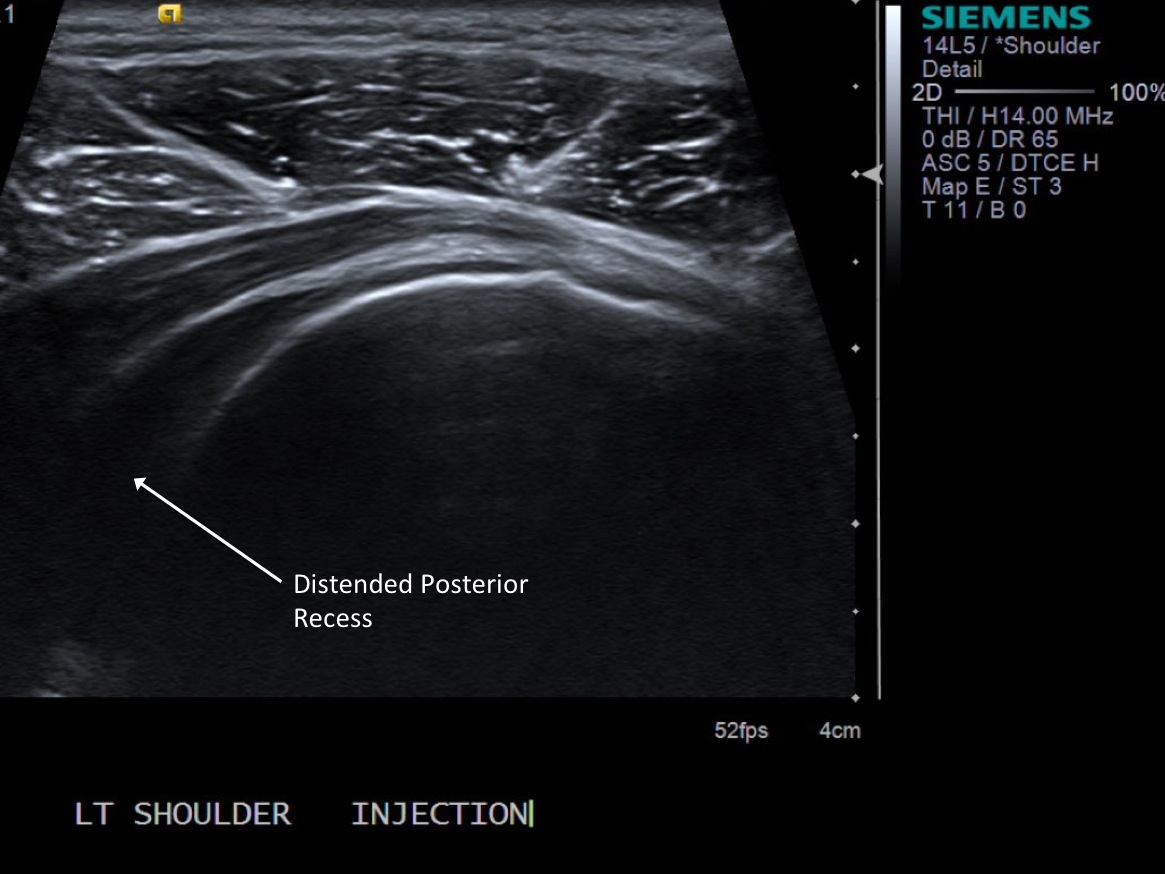

1. Standard pre procedure workup (consent, indications, contraindications, allergies, diabetes history, pain level 1-10)

• descriptiondescription